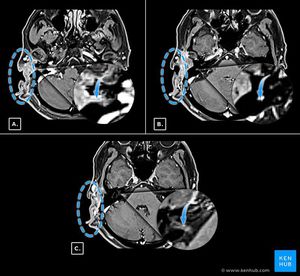

A43yr old male with (NF1)was seen because of a growing subcutaneous tumor of the right postauricular region .the tumor had been partially resected previously and had been shown histologically to be malignant peripheral nerve sheath tumor (MPNST)which presumably developed from a benign neurofibromatosis tumor .the patient didn’t have facial nerve paralysis or hearing impairment!!!MRI showed subcutaneous lesions from the enlarged stylomastoid foramen and also enlarged facial canal